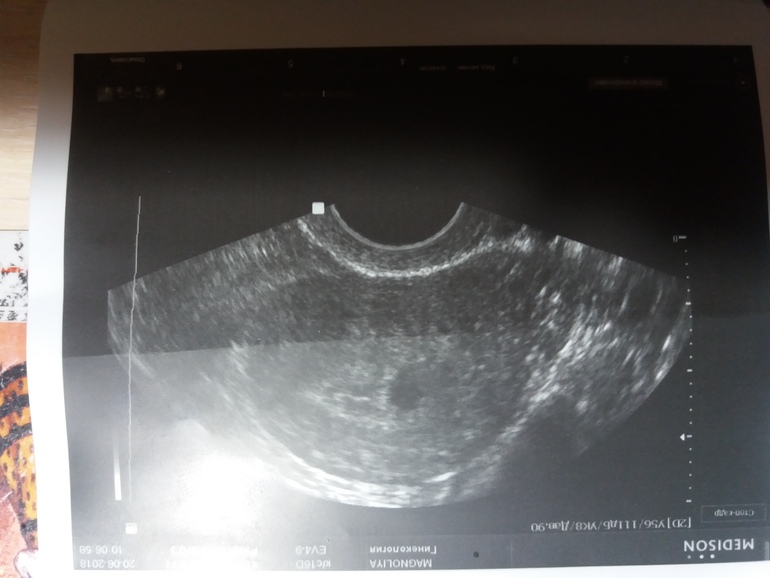

Такой вопрос. Была на узи малого таза ( направила эндокринолог исключить СПКЯ) там все Хорошо, но есть гипоэхогенное образование 9.1 мм.

Это не беременность. Полость матки не расширена, видна средняя линия смыкания листов эндометрия. Это пристеночное образование либо субсерозная миома, либо полип. Скорее всего, первое